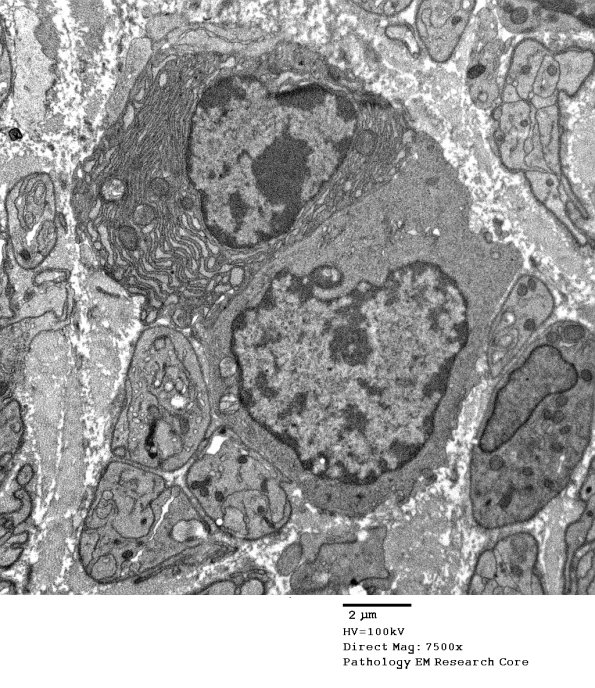

Endoneurial lymphocytes and rare plasmacytoid elements are also demonstrated ultrastructurally. (electron micrographs)